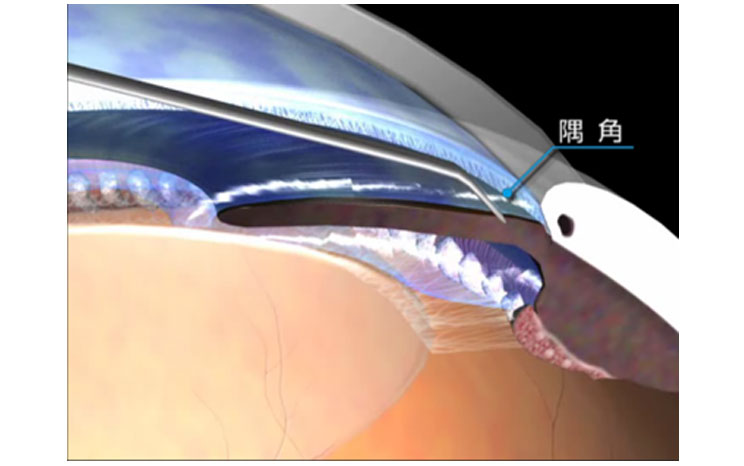

iStent®は開放隅角緑内障に対して眼圧を下降させる極低侵襲緑内障手術の際に使用されるMIGS(micro-invasive glaucoma surgery)デバイスです。単独での手術の際は自由診療となりますが、白内障手術と同時に行われる際には保険診療となります。

白内障手術の際に2.4mmの白内障手術創口からiStent®を線維柱帯にインプラントして、房水流出を妨げている線維柱帯に対して排出を改善し眼圧を下降させます。その為、侵襲の非常に少ない緑内障手術、極低侵襲緑内障手術として注目されております。臨床試験の結果では眼圧の下降と緑内障治療薬の低減が示されています。日本眼科学会HP[http://www.nichigan.or.jp/member/guideline/iStent.jsp]に詳細と論文がありますので、メリットデメリットなどご参考にして頂けますと幸いです。